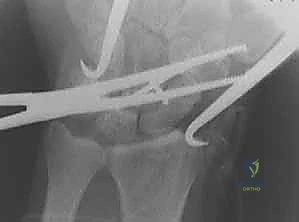

هذه هي الخطوة الأكثر حساسية. باستخدام أسلاك كيرشنر (K-wires) كـ "عصي تحكم" (Joysticks)، يقوم الدكتور هطيف بتصحيح تشوه DISI. يتم تدوير العظم الزورقي للخلف (تمديد) وتدوير العظم الهلالي للأمام (انثناء) حتى يتم استعادة الزاوية الطبيعية (46 درجة) وتختفي الفجوة بينهما تماماً.

5. الحفر وتمرير السلك الدليلي (Drilling & Guide Wire)

بمجرد التأكد من المحاذاة المثالية عبر جهاز الأشعة السينية اللحظي (C-arm Fluoroscopy) داخل غرفة العمليات، يتم إدخال سلك دليلي رفيع جداً يمر من العظم الزورقي مخترقاً إياه ليصل إلى العظم الهلالي في مسار دقيق للغاية.